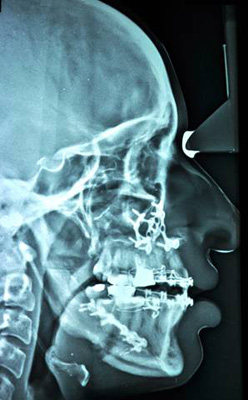

MAXILLARY LEFORT I ADVANCEMENT

BILATERAL SAGITAL SPLIT OSTEOTOMY SETBACK |

| Post-Op Profile |